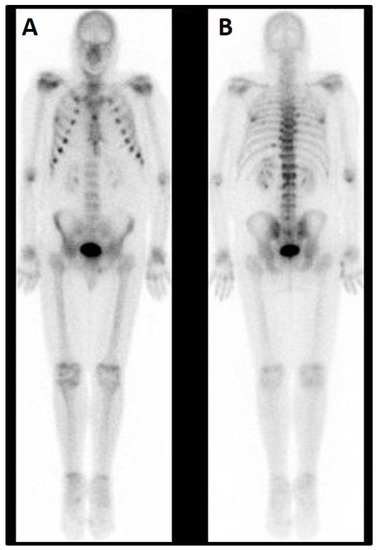

Total body scintigraphy revealed hypercaptation of rib-costal joints with a marked rosary sign at the chest, and some other mildly captating regions (Figure 1).

Figure 1. Total body scintigraphy (September 2015). (A) Front view. A Marked rosary sign at the chest. (B) Back view. Non-homogeneous spinal distribution of the tracer with increased uptake at the dorso-lumbar junction.